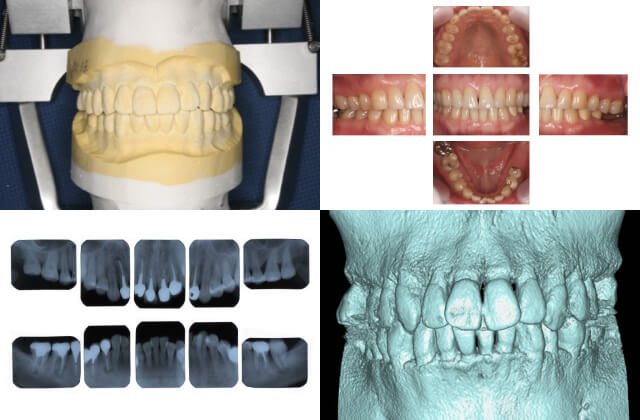

歯科ドック

当院では歯科ドックを実施しております。